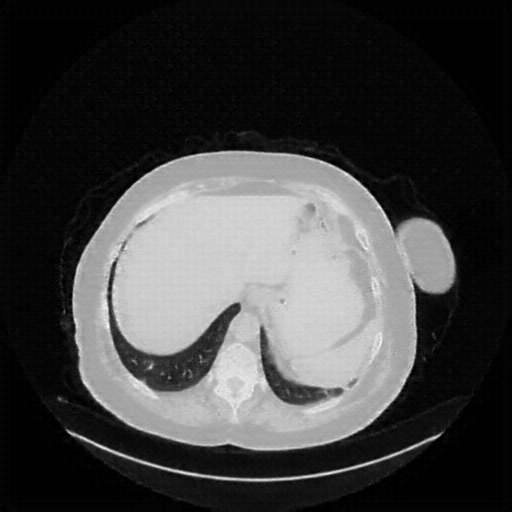

Original NATIVE CT scan (input)

Full window (WL 1023.5, WW 4095 β†’ Low βˆ’1024, High +3071)

Original VENOUS CT scan